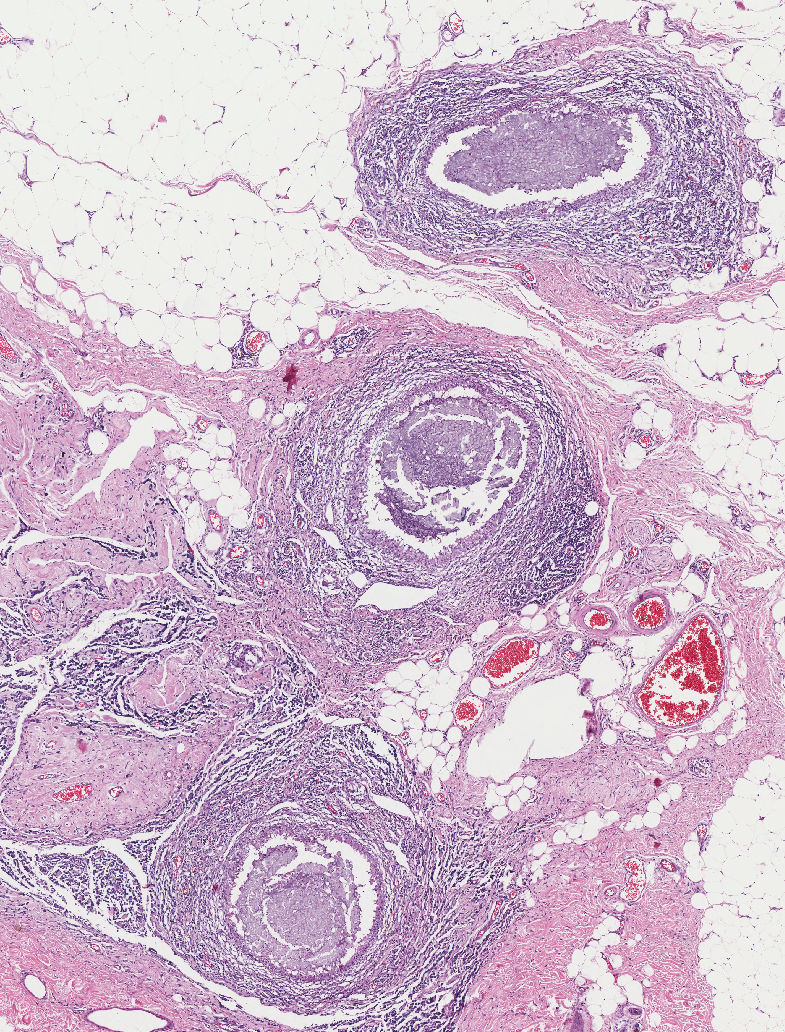

The three circular structures in the deep dermis and subcutis are most consistent with:

A) Migrating parasites

B) Plant material (e.g. wood foreign body)

C) Braided absorbable suture

D) Dilated ducts of glands with surrounding inflammation

A

14

Q

How long have the circular sutures been in the tissue:

A) A few days

B) At least 2 weeks